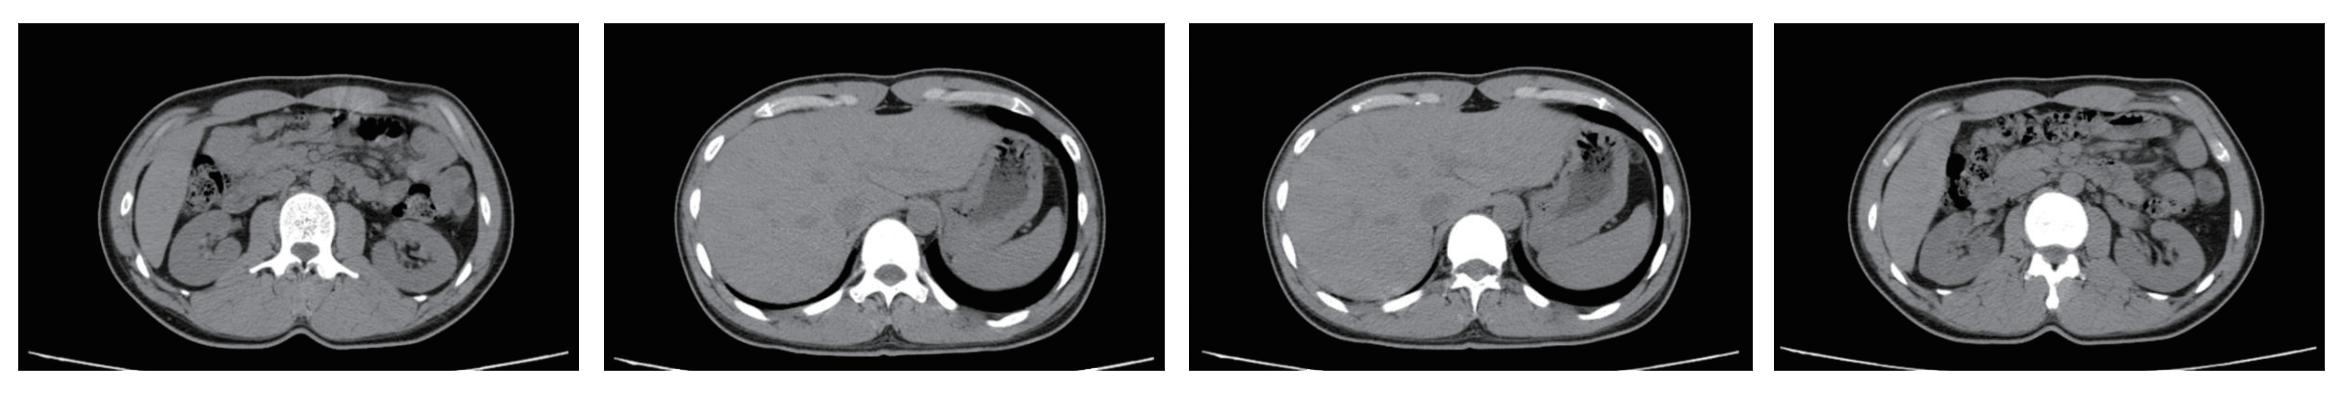

Abdomen